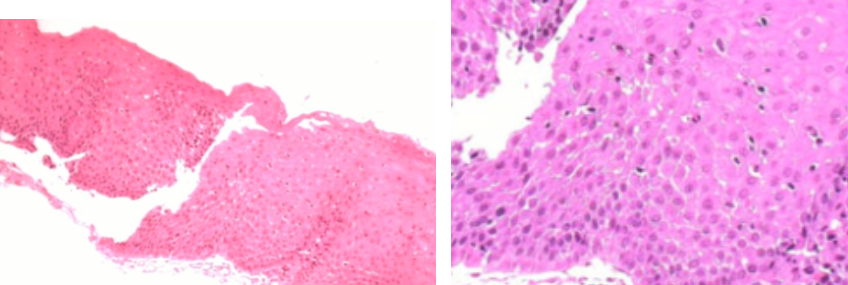

Reflux oesophagitis

Eosinophilic oesophagitis